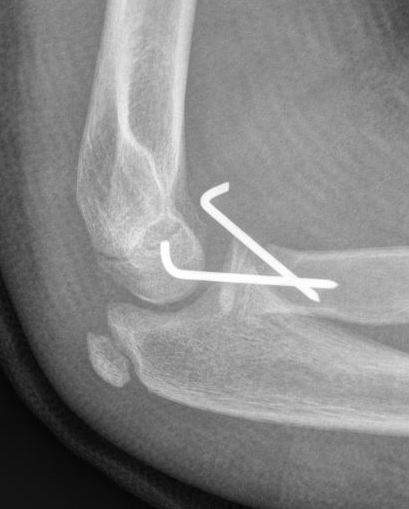

Xray

Displaced and angulated radial neck fracture

Percutaneous K wire

Technique

Pronate arm to protect PIN

- insert into fracture site

- lever fracture into reduced position

- then drive into opposite cortex